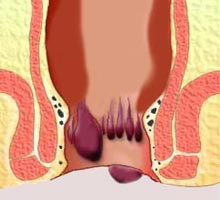

Distinguimos dos tipos de hemorroides, las internas, que son las que se sitúan por encima del conducto anal y se encuentran cubiertas por mucosa, por lo que no se visualizan en una inspección externa de la zona; y las externas, que son las que mas comúnmente podemos ver, al situarse por debajo de la unión anorrectal y estar recubiertas de piel.